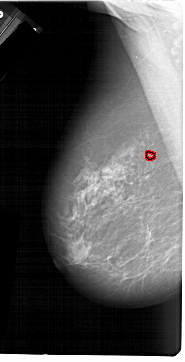

A_1214_1.LEFT_MLO

FILE: A_1214_1.LEFT_MLO.OVERLAY

TOTAL_ABNORMALITIES 1

ABNORMALITY 1

LESION_TYPE CALCIFICATION TYPE PLEOMORPHIC DISTRIBUTION CLUSTERED

ASSESSMENT 4

SUBTLETY 4

PATHOLOGY MALIGNANT

TOTAL_OUTLINES 1

BOUNDARY